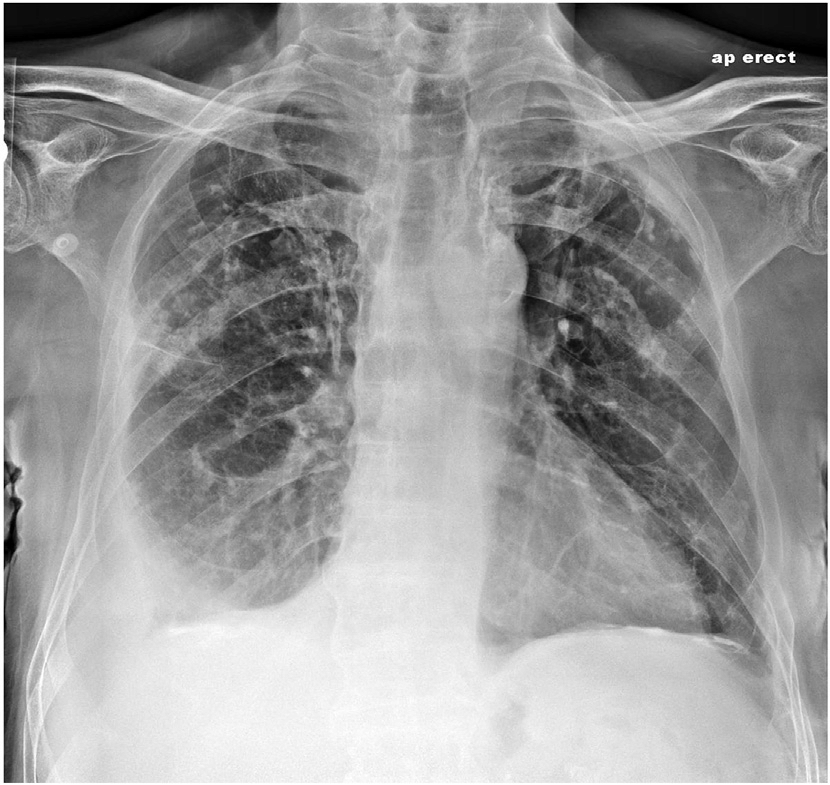

- 영상 검사 : 흉부 X선, CT 스캔 등을 통해 염증의 정도나 기타 이상을 평가합니다.